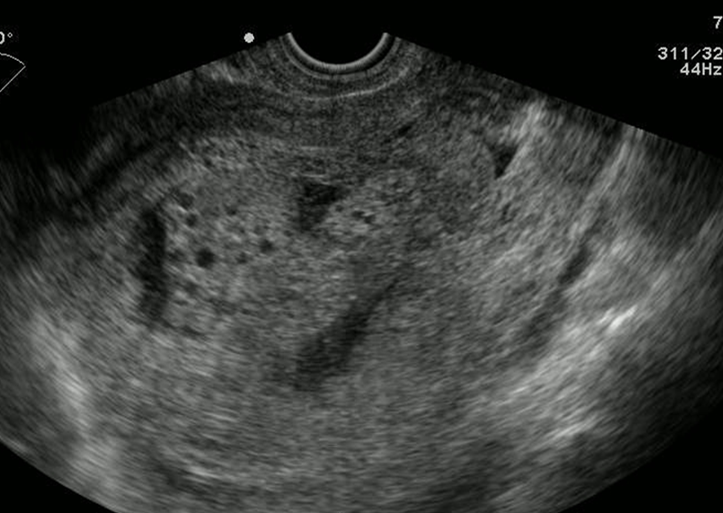

妊娠6週の胎嚢とEFS

図は、妊娠6週の胎嚢とEFSが描出されたものですが、よくみると後壁の子宮内膜(脱落膜)に絨毛膜が着床している様子がわかります。そして、前壁と後壁の脱落膜の間にEFSがあるように見えます。これは、前後の子宮内膜の間にたまった液体貯留である可能性が考えられます。しかし、これだけでは水か出血かの鑑別はできません。